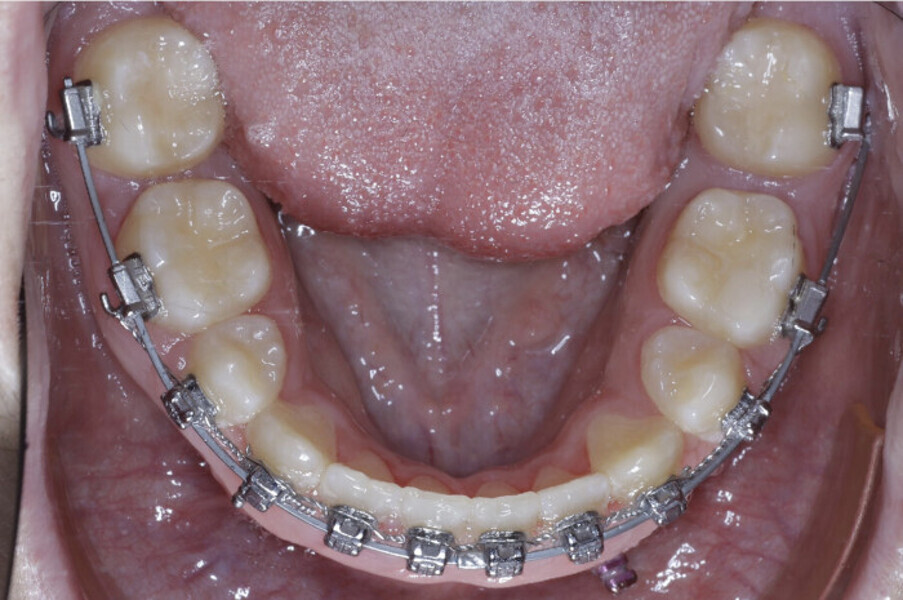

New Age orthodontics and orthopaedics with temporary anchorage devices